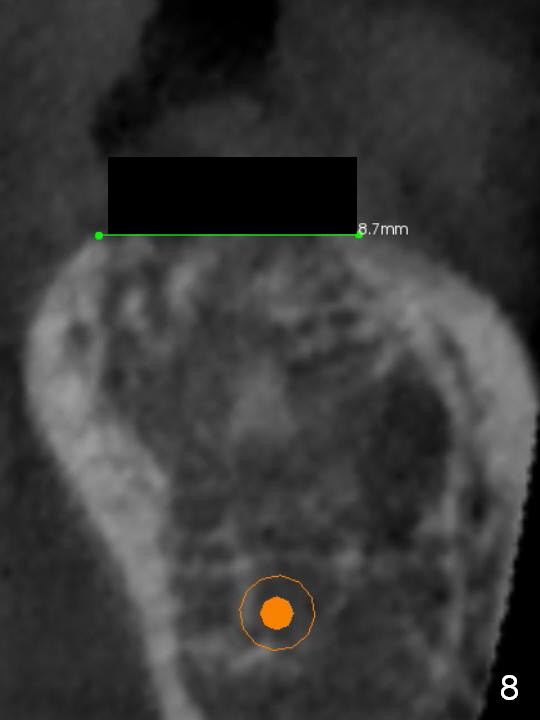

To bury the implant evenly, the ridge should be flattened (Fig.8) prior to osteotomy and implant placement (Fig.9) when bone height is sufficient.